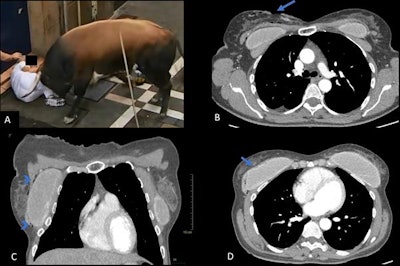

Crushing is another typical scenario. In San Fermín, the most tragic crushing occurred in 1977, with one person dying of asphyxia, and again in 2013, after a door was left open too long and participants started to pour down the alley, a critical area of the route.

"That was a real catastrophe, but surprisingly few people were severely injured in the end. This could have been much worse," Miranda recalled.

One of the casualties was notably resuscitated onsite and then sent to the emergency department. CT showed that he had multiple rib fractures, pulmonary contusions, mild right pneumothorax, and pericardial effusion, probably due to cardiorespiratory arrest.